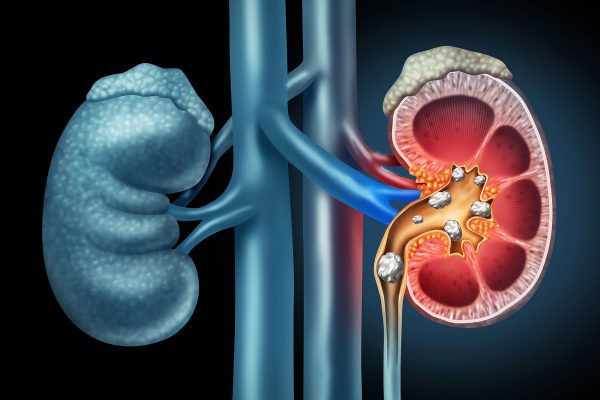

1800ss_getty_rf_kidney_stones

Urinary Stones (Kidney and Bladder)

Stones can cause pain, infections, or blood in the urine. Treatments include laser stone fragmentation (ureteroscopy), shockwave therapy (ESWL), and keyhole surgery (PCNL) for complex or larger stones. PCNL and ESWL would be referred to the NHS due to the specialised facilities required.